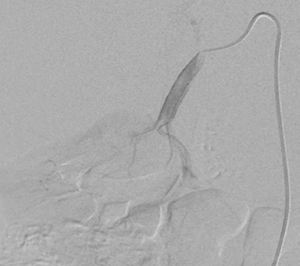

右副腎腫瘍摘出の栄養血管推定術前シミュレーションとして,造影CT,腹部アンギオを行った。アンギオの結果,副腎腫瘍には右横隔膜下動脈,右肝動脈からの分岐右副腎動脈,腰動脈などから多数の栄養が認められた(図1)。さらに,右腎動脈遠位付近より副腎腫瘍に上行する血管を確認したため,右腎動脈を選択造影したが(図2),どこから分岐しているのかアンギオ,造影CTのVR処理,MIP画像,MPR画像のいずれでも推定が困難であった(図3,4)。

図2 右腎動脈の選択造影画像 |